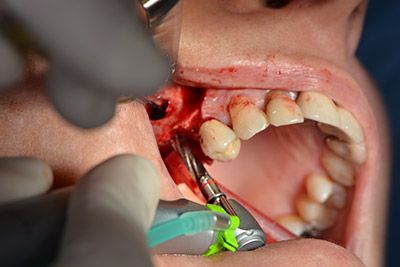

Im nächsten Schritt wird die Sinusbodenelevation mit simultaner Implantation durchgeführt. Für die bukkale Fensterung der Kieferhöhlenwand gibt es auch hier bei der Implantmed an der ersten Position eine Voreinstellung.

Mit 35.000/min wird das Fenster angelegt und anschließend die Schneidersche Membran nach kranial präpariert. (Abb. 13 bis 14).

Danach wird das Implantat eingebracht und der Knochen aufgebaut. Aufgrund der Größe des Augmentates wurde im vorliegenden Fall Eigenknochen, der als Bohrspäne bei der Implantation 16 und der Fenestration 14 angefallen ist und mit einer Knochenfalle aufgefangen wurde, mit Knochenersatzmaterial vermischt.

Eine resorbierbare Membran bildet die Barriere nach bukkal und deckt das Augmentat ab. Zum Schluss wird speicheldicht vernäht. (Abb. 15 bis 19).